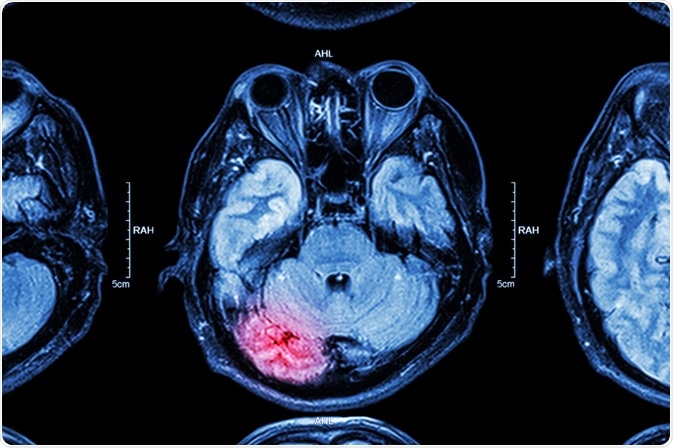

Monitoring brain injury

The U.S.A. alone witnesses over 50,000 deaths as a result of brain trauma. This type of sensor is likely to see widespread use, in order to pick up early signs of brain swelling, that could, if untreated, lead to irreversible brain injury, and either death or a vegetative state.

brain injuryImage Credit: Puwadol Jaturawutthichai / Shutterstock.com